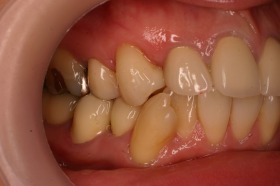

今まで気になっていた前歯の差し歯や奥歯の銀歯をセラミックにて治療しました。

噛みやすさや患者さんの経済状況から一気に治療するのではなく、段階的に治療しました。

そのため実際には目立ちにくい、上の奥歯などはまだ銀歯になっている状態です。